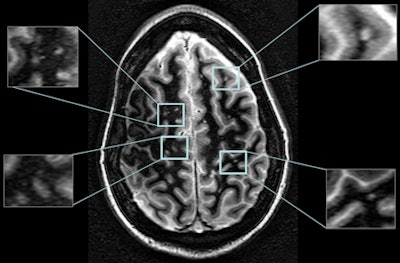

"The high spatial resolution and excellent gray-matter/white-matter contrast allowed depicting a number of juxtacortical [adjacent to the cerebral cortex of the brain] lesions and a few gray-matter lesions," Sammet said.

Furthermore, a dark outer ring was observed on some lesions on SWI phase images that was not visible in SWI magnitude or white-matter attenuated images. Most lesions visible on SWI magnitude and phase images were associated with venous vasculature.

Based on the results, Sammet and colleagues were very encouraged that 7-tesla MRI could provide several novel contrast imaging sequences to visualize and characterize multiple sclerosis lesions. It can also differentiate the lesions' substructures not typically visible at 1.5- or 3-tesla MRI.